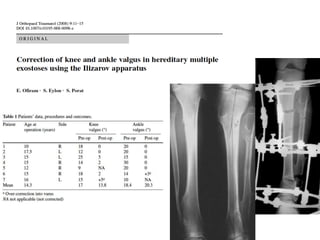

Rodilla  Genu valgo

• 8 – 33% de los pacientes

• Asocciado a Nº y tamaño

de lesiones en rodilla

• Shapiro et al.

– Deformidad de la tibia sería

principalmente responsable

del genu valgo

• Nawata et al.

– Perone acortado

desproporcionado con

respecto a la tibia sería el

responsable del genu valgo

Rodilla

• Alternativas de tratamiento

• Shapiro et al.  OTT

correctora con buenos

resultados esteticos y

funcionales

• Cuña de apertura femoral,

hemiepifisiodesis tibia, OTT

tibial alta

– Ex clinico normal, mantención

de eje mecanico

– Artrosis futuro?